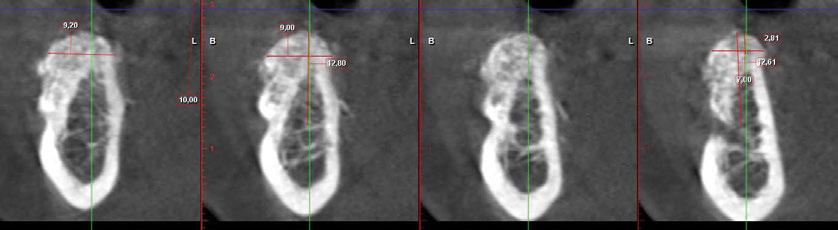

y lo que se pudo preservar del hueso malar. Se añadió una malla sinterizada infraorbitaria para dar volumen a la mejilla y se planificaron dos brazos de conexión que emergieran en las posiciones 24 y 26 de forma subgingival (Figuras 8 y 9). La superficie interna que apoyaba en el hueso era de titanio microrrugoso, y la superficie externa y conectores de titanio pulido y hexágono externo universal (Figuras 10 y 11). La cirugía se hizo bajo anestesia general en infiltración con anestesia local (4% articaína, 1:100.00 epinefrina), levantando el

colgajo cutáneo de la mejilla por vía intraoral, preservando el colgajo temporal para no comunicar con el remanente de la cavidad naso maxilar (Figura 12). Se emplearon 10 tornillos de osteosíntesis de 1,9 mm y la estabilidad primaria obtenida fue excelente (Figura 13)